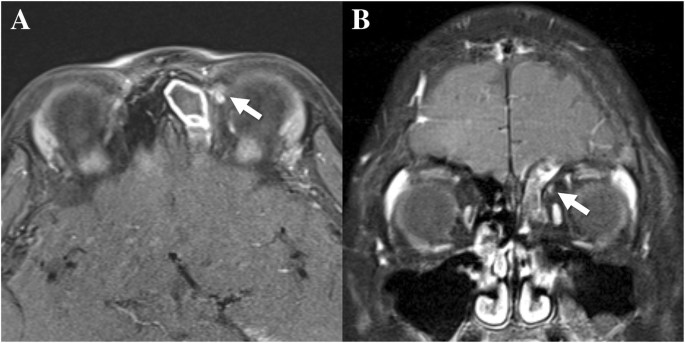

An 8-year-old boy presented with left periorbital pain for a week. His parents reported that he had mild headache intermittently when he contracted upper respiratory infections but was otherwise healthy. His uncorrected visual acuity was 20/20 in both eyes with mild hyperopia. Ductions and versions were normal, although there were 10 prism diopters of intermittent exotropia as determined by prism and alternate cover testing. There was no pain on eye movement. However, the patient presented intense tenderness on palpitation over the left trochlear region without swelling or redness around the left periorbital area. Orbital magnetic resonance imaging (MRI) showed focal enhancement on the left trochlea (Fig. 1). Left frontal, ethmoidal, and maxillary sinusitis was also detected. The patient, however, had not been previously diagnosed with sinusitis. We referred the patient to an otorhinolaryngologist. On rhinoscopic examination, the patient presented mild rhinorrhea with posterior nasal drip, and the mucosa was swollen in the left middle meatus. He underwent treatment with oral empirical antibiotics (amoxicillin/clavulanate syrup for 9 days and then cefpodoxime syrup for 4 days), leukotriene receptor antagonist, and steroid nasal sprays to control the sinusitis and rhinitis. The symptoms and signs were completely resolved after a course of treatment without the need for local steroid injection in the trochlear area. There was no recurrence during the 8-month follow-up period.